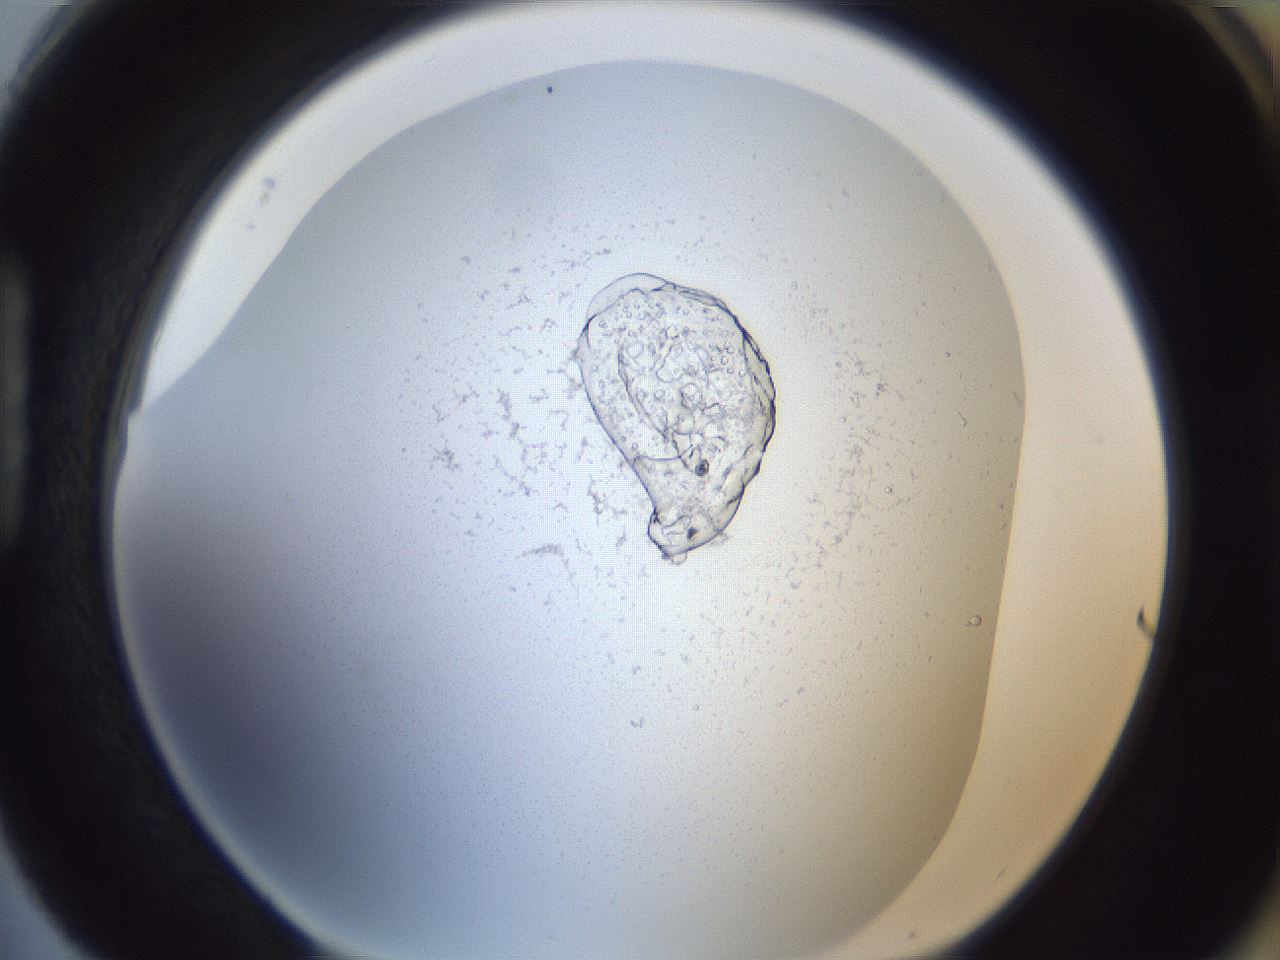

folderID217_plateID1217_batchID3671_wellNum88_profileID1_d1_r68942_ef.jpg